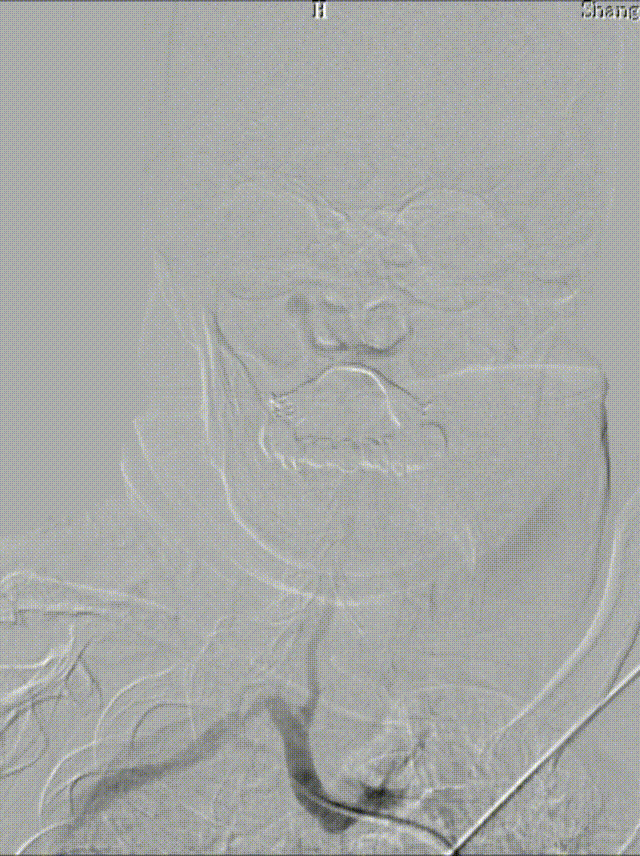

0.018*300cm 外周导丝至左肱动脉,0.014*200cm 通桥北斗SS™神经血管导丝超选至左椎V2段远端。

沿0.018*300cm 外周导丝送入6*40 外周球囊送至左侧锁骨下动脉狭窄处,压力泵逐渐加压到6atm。

撤出球囊后见残余狭窄40%。

再次沿0.018*300cm 外周导丝送入6*40 外周球囊达LSub狭窄部位,压力泵逐渐加压到8atm,见残余狭窄20%。

造影见LV闭塞,立即沿0.014*200cm 通桥北斗SS™神经血管导丝置入3mm*16mm 药物球扩支架至LV1。

压力泵逐渐加压球扩支架到8atm, 支架打开良好,造影示残余狭窄0%。